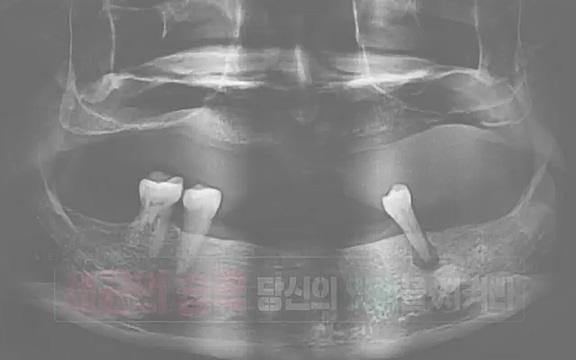

조영단| 서울대치과병원 치주과 교수. 치아머리 아래쪽 뼈가 이렇게 둘러싸고 있어 줘야되는데

![[792회] 생로병사의 비밀 - KBS[세균의 습격, 당신의 잇몸을 지켜라!] 감기보다 병원을 더 자주 찾게 만드는 질병이 있다. 바로 치주질환이다. 2020년 외래 다빈도 질병 1위를 차지한 치은염 및 치주질환 환자는 1,637_20220505_140504.350.jpg](https://blog.kakaocdn.net/dn/btihbw/btrBjJaPqit/wp6mR6snaXQPSK9XxnTYwK/img.jpg)